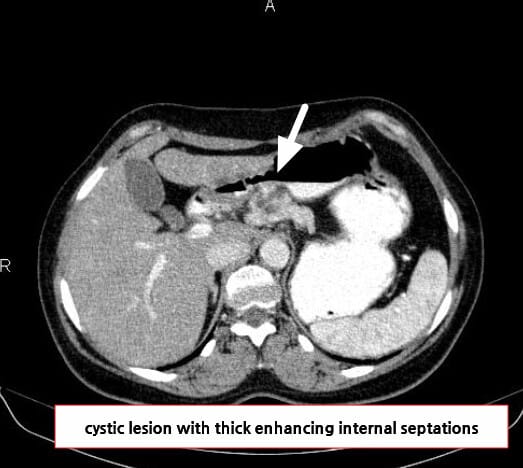

영상 소견

벌집 모양(microcystic) 낭종, Central scar, 석회화 등

| 🟦 Microcystic pattern |

| 수 mm 크기의 다수의 낭종이 집합된 형태입니다. |

| 🟦 Central scar with calcification |

| 중심에 석회화를 포함한 반흔이 특징적으로 관찰됩니다. |

Niknejad M, Pancreatic serous cystadenoma. Case study, Radiopaedia.org (Accessed on 18 Jul 2025) https://doi.org/10.53347/rID-85866